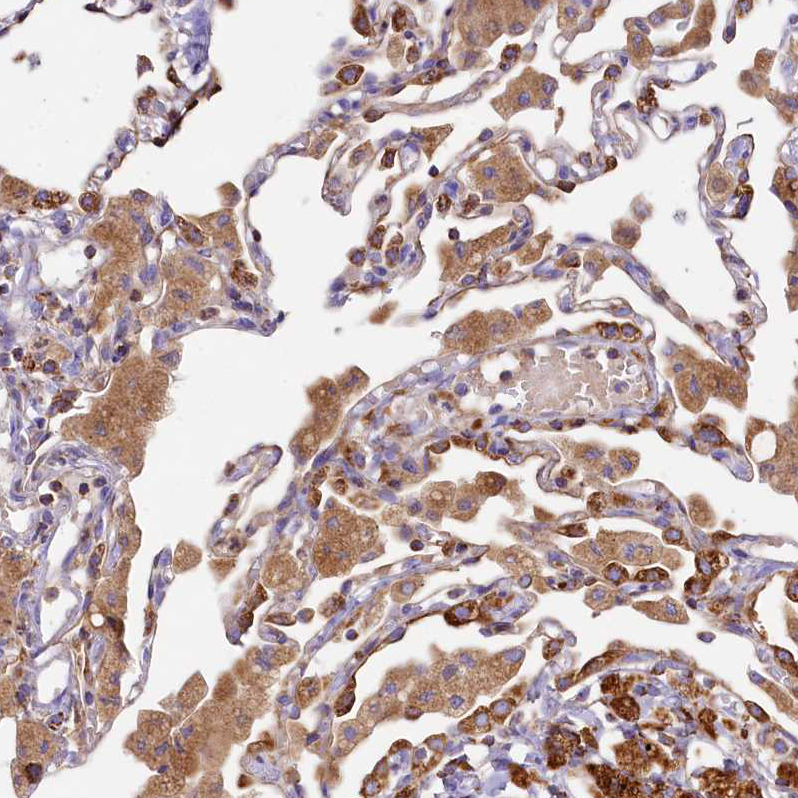

Immunohistochemical staining of human gastrointestinal, kidney, liver and lung using Anti-CLYBL antibody HPA040691 (A) shows similar protein distribution across tissues to independent antibody HPA039959 (B).